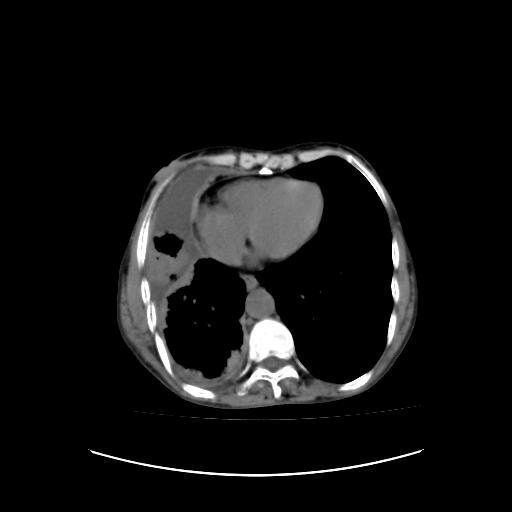

可见多发肺内病灶,且胸膜病灶较多有圆球状而非丘状,多考虑胸膜转移瘤伴胸腔积液,右侧胸廓缩小固定,且部分病灶呈丘状,尚不除外恶性胸膜间皮瘤伴肺内转移

右侧胸膜增厚,局部呈结节状增厚,右侧胸腔少量积液。双肺未见确切肿块影。纵隔未见淋巴结肿大。气管、支气管通畅。考虑右侧胸膜间皮瘤(恶性?)可能性大。不除外癌性胸膜炎。

恶性胸膜间皮瘤伴肺内转移可能性大;或胸膜、肺内均为转移瘤,左肺下叶亦见多发小结节影。

右侧胸廓塌陷,右侧胸膜广泛增厚并见多发胸膜结节,右侧少量胸腔积液并包裹。

右侧广泛胸膜增厚,局部呈结节状增厚,右侧胸腔少量积液。双肺未见确切肿块影。纵隔未见淋巴结肿大。气管、支气管通畅。考虑右侧胸膜间皮瘤(恶性?)可能性大。支持!

右胸腔结节均考虑来自胸膜(部分来源于叶裂),考虑胸膜间皮瘤或转移瘤.